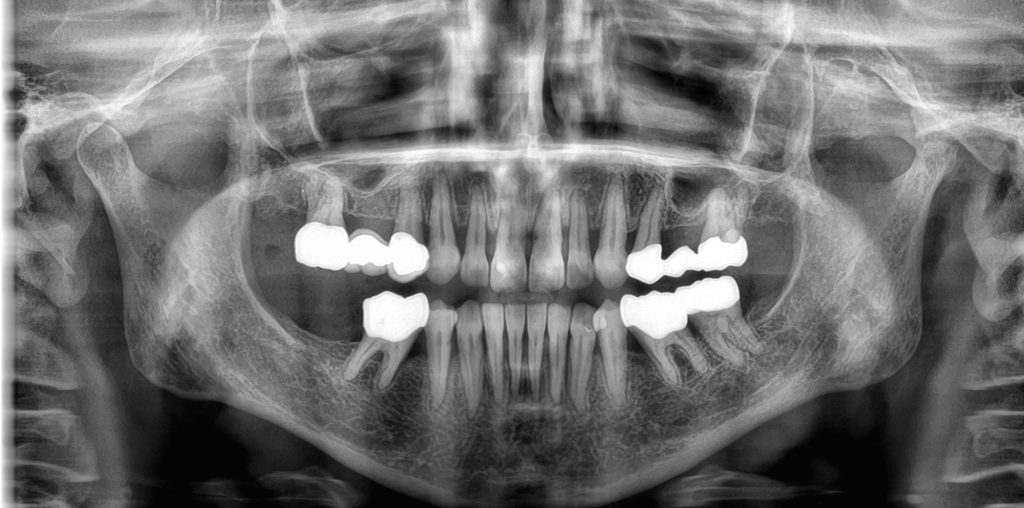

cs82003d-klinikes-eik-04 Published 14 February 2021 at 2000 × 992 in cs82003d-klinikes-eik-04 ← Previous Next →